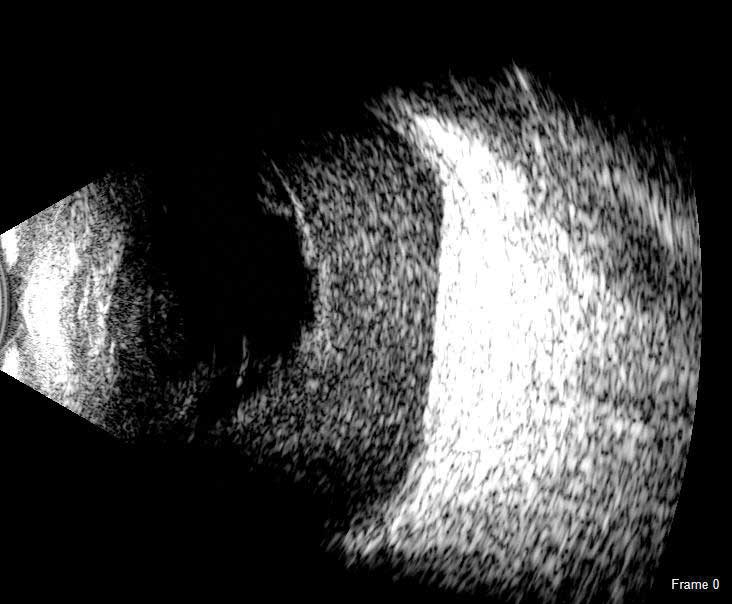

The DGH 8000 B-Scan combines the most advanced ultrasound technology available with the processing power, data storage and connectivity advantages of a personal computer. The DGH 8000 is equipped with dual 12.5 MHz and 15 MHz frequencies in the same probe, which results in a unique depth selection range from 3 cm and 6 cm in 12.5 MHz mode and 5 cm and 10 cm in 15 MHz mode.

It is a self-contained portable imaging system that interfaces with a Windows® computer via a USB 2.0 port. High resolution video loops and still images are obtained rapidly, and post processing features include playback, gain adjustment, contrast and image intensity variation, distortion-free zoom, distance, angle and area measurement and annotation tools. Patient data can be stored on a local computer or on a centralized network location where it can be accessed by multiple users. Patient records are fully searchable and can be exported in a format that is compatible with EMR/EHR systems.

The DGH 8000 B Scan delivers clear images for the posterior portion, even when optical clarity is compromised:

- Retinal Detachments

- Vitreous Detachments

- Vitreous Humor Pathologies

- Staphylomas

- Posterior Segment Pathologies

- Choroidal Pathologies

- Optic Nerve Pathologies

- Scleral Thickening